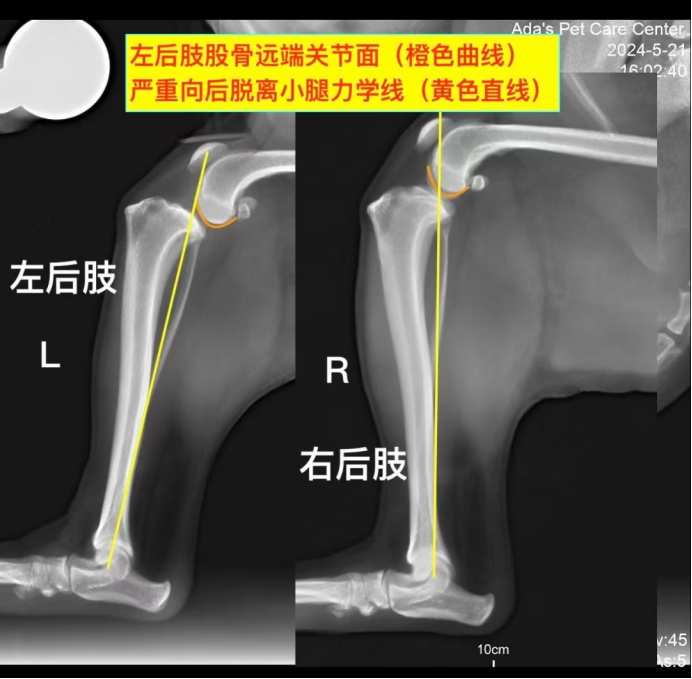

由于狗狗在清醒状态下无法进一步进行检查,孙医生决定进行镇静麻醉。通过镇静后,详细检查中发现左后肢的抽冠试验呈阳性,明确提示前十字韧带断裂。同时,膝关节的X光检查显示在受力状态下,股骨和胚骨处于半脱位状态。最终确诊为左后肢前十字韧带断裂。